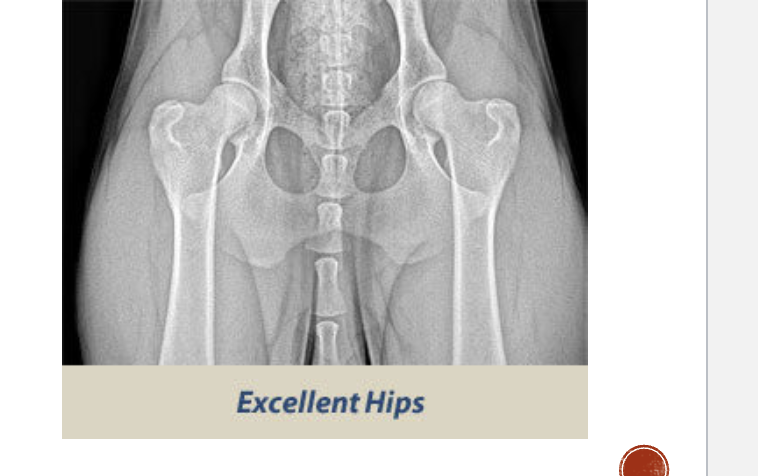

Orthopedic foundation for animals

OFA normal classification

Excellent- deep seated ball that fits tightly into a well formed socket

Good- well formed congruent hip joint visualized. The ball fits well into the socket and has a good coverage present

Fair- hip joint is wider. the ball slips slightly out of socket. Socket can appear shallow